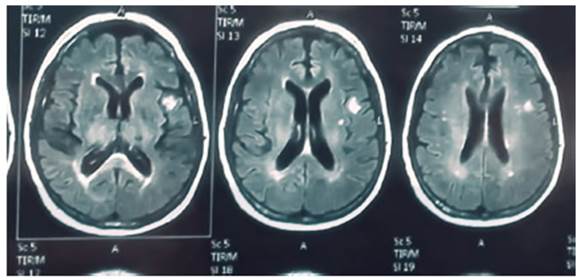

+ trimethoprim–sulfamethoxazole (TMP-SMX). Brain MRI (magnetic resonance

imaging): the left subcortical temporal region shows hyperintense 10 mm nodular

lesion with ring enhancement and restricted diffusion, consistent with an

abscess (Fig. 2).